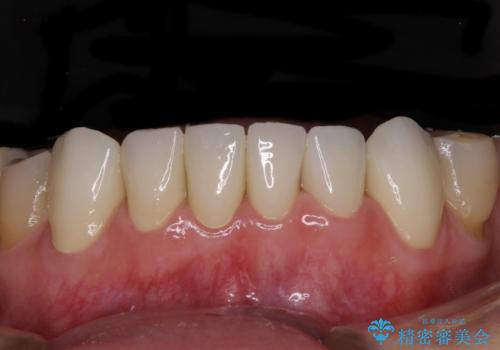

歯周外科処置を行ったことで歯周ポケットはなくなり、毎回のブラッシングの度に嫌な思いをしていた出血は認められなくなりました。

上下前歯の見え方を気にされており、歯だけをみると大変長くなりましたが、笑ったときの口元は自然な外見となり、患者様には大変満足していただきました。